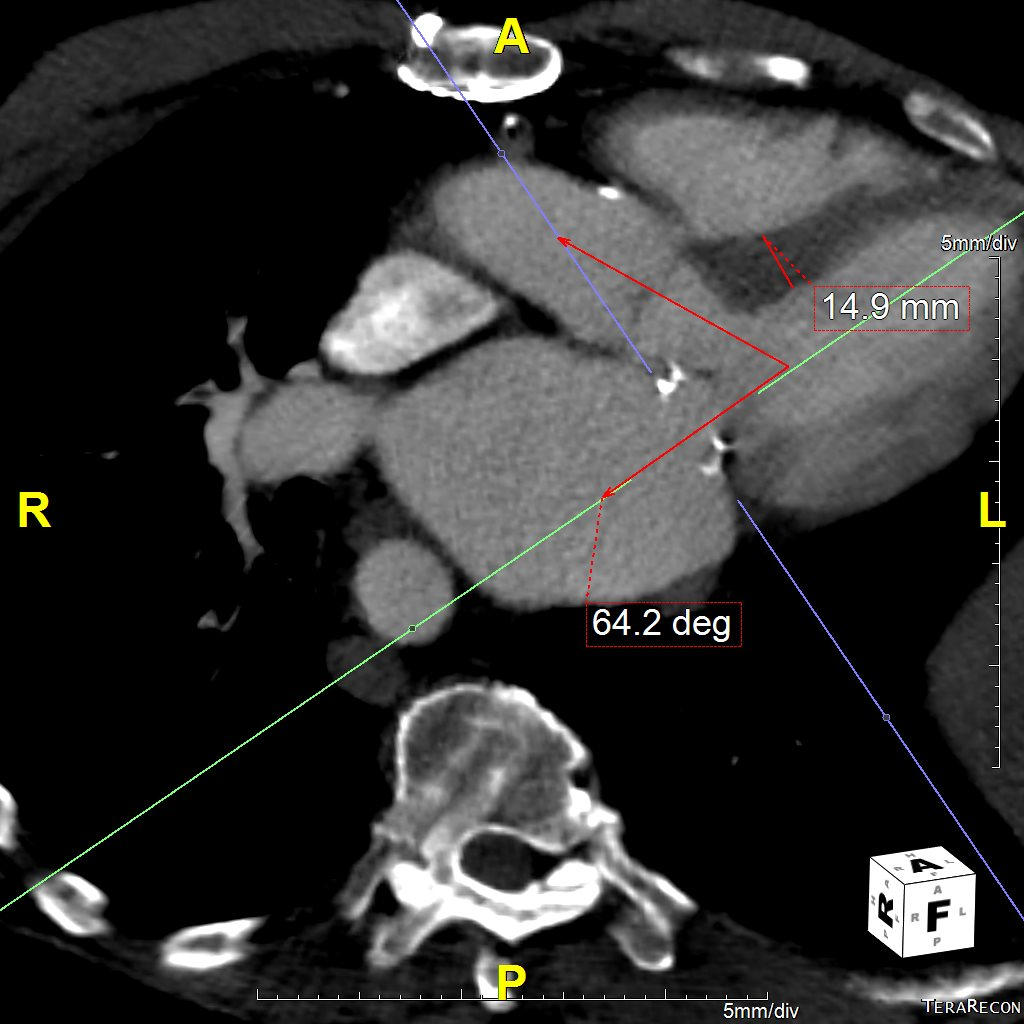

Six months later, the patient had continued shortness of breath and a transesophageal echocardiogram revealed severe mitral regurgitation with evidence of mild peri-prosthesis leak (video 2). Due to his elevated surgical risk (STS score of 9%),patient underwent a valve-in-ring (ViR) transcatheter mitral valve replacement (TMVR) with a 29mm Edwards Sapien3 via a trans-septal approach (using 14mm balloon for septostomy). Pre-procedure planning was done based on transthoracic & transesophageal echocardiography and multi-detector CT (without measurement of neo-LVOT with a simulated valve) showing long anterior leaflet (27mm), thick interventricular septum (1.5cm), LVOT diameter (1.8cm), aorto-mitral angle of 64 degrees (Figure 1, video 1). Immediately post TMVR, patient did well with stable hemodynamic but over next 2-3 days systemic pressures started to drop along with decline in renal function was noted. Trans-thoracic echocardiogram showed systolic anterior motion (SAM) of the anterior mitral leaflet with elevated LVOT gradient of 88mmHg (baseline LVOT gradient of zero mmHg prior to TMVR). Furthermore, there was evidence of a continued iatrogenic atrial septal defect with continuous left to right shunt. Percutaneous left ventricular assist device (Impella CP) was placed for hemodynamic support for 24 hours with improvement in renal function. The patient underwent alcohol septal ablation of 1st large septal perforator (injected 1.5ml of pure alcohol) with drop of LVOT gradient from 80 mmHg to 20mmHg. Next further septal ablation was performed by injecting another 1 ml of pure alcohol into the basilar branch of 2nd septal perforator with final LVOT gradient of 10mmHg (video 3).The patient was able to be discharged and his renal function recovered, however, he still continued to have NYHA functional class III symptoms.

Figure 1 Pre-mitral valve replacement multi-detector CT scan showing thick interventricular septum and aorto-mitral angle (panel A), and transesophageal echocardiogram showing long anterior mitral leaflet and left ventricular outflow tract diameter.